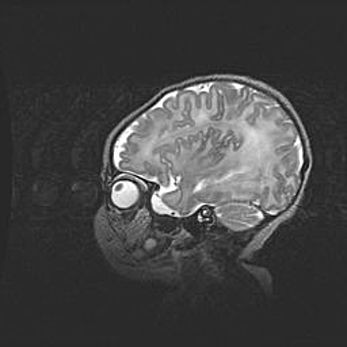

Неполная лизэнцефалия (пахигирия). Открытая гидроцефалия.

Возраст: 17 дней

Вес: 3110 г

Пол: мужской

Окружность головы: 33,5 см

Срок гестации: 35-36 недель

Лизэнцефалия—недоразвитие корковой пластинки и мозговых извилин в результате нарушения миграции нейронов коры. Поверхность мозговых полушарий гладкая. Микроскопически выявляется отсутствие нормальных слоев коры и скопление групп нейронов в подкорковом белом веществе.

Пахигирия—уменьшение числа вторичных извилин. В пораженном полушарии нервные клетки образуют толстый недифференцированный слой с неправильно расположенными нервными волокнами и группами гетеротопных клеток. Нервные клетки незрелые. Белое вещество истончено. При этом нередко аномально развит корково-спинномозговой путь.